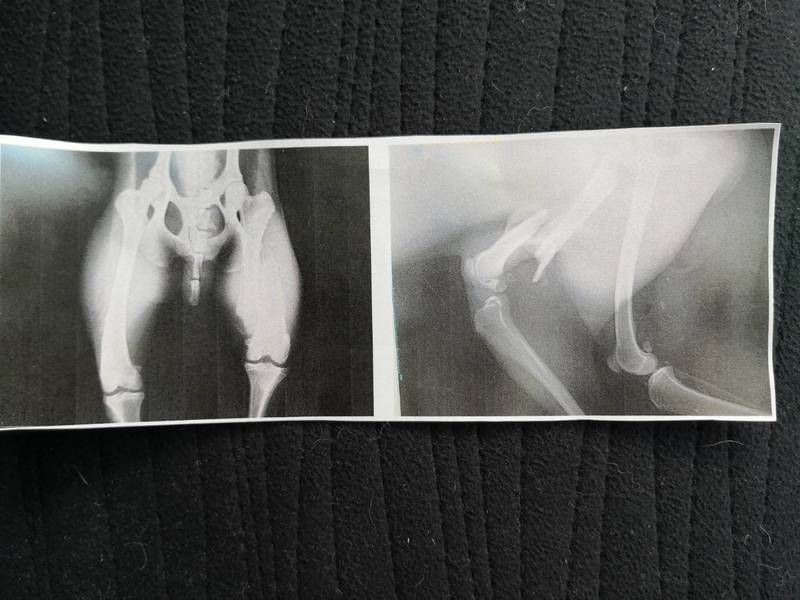

| 特徴(性格など) | この子は山口県周南市の広い敷地で野良犬状態になっている子達が多数いる現場で、捕獲檻に入り保護されました! まだ1〜2歳位の中型雑種、キラキラの綺麗な瞳の可愛い可愛い男の子、かなりのビビリ君です。 収容時には足を地面に着くのを痛がる素振りがありました。 (センター収容時の動画をご覧下さい) 検査の結果、大腿骨骨折後とのことでした。今は新しい骨が出てきていますが、足は上げて歩くようです。 劣悪な環境の中、足の痛みに耐え頑張ってきたこの子を幸せにしてくださる家族に繋げてあげたいと思います。 現地ボランティアが、殺処分寸前で引き出し、自宅へ連れ帰りシャンプー、医療をかけてくださいました。 次から次に収容が絶えない周南市のため、ボランティア宅に一時的に預かっていただき、現在は防府市のシェルターで、人馴れの練習と本当のずっと一緒の家族を待っています。 ただシェルターも犬でいっぱいのため、このままでは、命の期限がある子達を守ってあげることができない状況です。 生まれてから一度も首輪もした事が無く、人と一緒にリードを付けてのお散歩もした経験がない子です。 僅かなご飯だけ与えられ、撫でられたり触れ合ったり、人からの当たり前の愛情を知らぬまま、ビックリする劣悪な環境の中で暑さ、寒さ、雨風にも耐えるしかなく必死に生きてきました。 それでも、そんな環境のままでいたより、保護されたことは良かったと考え、この子の幸せを、温かい本当の家族を見つけたい!と願っております。 人と暮らした経験がない上に、突然シェルターに連れて来られ、何もかもが初めての環境になるので無理もありませんが、可哀想にかなり怖がっています。 しかし、最近ではおやつを手からも食べてくれたりするようになってました! シャンプーも問題なくさせてくれました! しかし、人や新しい環境に馴れるまではまだ時間を要すると思われます。 お散歩デビューもまだできていません。リードを着け、犬舎から連れ出そうとしても、とにかく隠れようとして縮こまってしまい、毎日楽しい事は何もない日々、時間を過ごしているのだと思います。 栄養状態も悪かったので、やや痩せ気味、体重は15.6キロ位です。 まだまだ若い子ですし、色々不安で、この子にとっては怖い事ばかりなのでしょうから、人間が焦らずゆっくりゆっくり長い目で見守りながら、根気よく愛情を持って接すれば、いつかきっと!徐々に心を開いて新しい家庭に馴染んでいけるのでは、と思います。 シェルターではこの子だけに時間を割いてあげる事ができず、人馴れ訓練もなかなか進まない状況です。少しずつ、人の目を見てくれるようになり、ビクビクしてお腹にくっつくほど巻き込んでいた尻尾をクルンと上向きに振ってくれたりもするようにはなってきました! ちょっとずつちょっとずつですが、当初に比べたらこの子は分かってきてくれています。 人は怖くないんだよと、人を信じてくれるように、広い心で長期戦ドンとこいと仰って頂ける方、まだ怯えていて不安気な困り顔のこの子を、いつか尻尾フリフリ♪ニコニコの笑顔にしてくださる方、このような状態の子を迎えてくださる自信のある方、いらっしゃいませんか? 生まれてきてから辛い事ばかりだったこの子にどうか温かい手を差し伸べてください! どうぞ宜しくお願い申し上げます。 ⭐️必ず室内飼育で、万全の脱走防止策をしていただける、なるべくお留守番時間が少ない、たくさん優しく触れ合ってくださるご家庭。 ⭐️ 首輪や胴輪、お散歩はおろかリードを付けた経験すらありませんでした。 トイレの躾も1からとなります。まだ人前で排泄する事もできず我慢しているようです。人の気配がない時にしています。 何かと手がかかり大変ですが(マナーベルトやL字型のトイレ、ペットシートを用意など) 覚悟と理解で受け入れて下さる方 ⭐️この様な犬の飼育経験があり愛情を持って犬をしっかり躾することが出来る方、当分はまだお散歩ができないと思われますが、室内での練習から始め、今後、運動に充分時間をあてられる方、場合によりトレーニング教室なども視野に入れて考えてくださる方。 何卒宜しくお願い致します。 以上の点を踏まえ、この子の置かれてきた状況をご理解のうえ、全て受け入れ寄り添っていただけるご家庭で可愛がっていただきたいと祈っております。 この子は身勝手で無責任な人間達による被害者であり、何も悪くありません。 家族の一員として生涯大切にしてくださる優しいご家庭とのご縁が結ばれ幸せになれますように。 これからのこの子の幸せを心から願っています⭐︎⭐︎ 外飼いではなく、室内飼育で家族の一員として迎えてくださる方、お手数をお掛けしますが「引き渡し」方法の欄にあります 【アンケート】にご回答と共にご応募いただけますようお願い致しますm(_ _)m https://www.koinuno-heya.com/suteinu/index.html#three-one https://youtu.be/rC3jqFa-TB4 ■応募地域に関して 遠方の方もできる限りの対応を考慮致しますので、応募時にお問い合わせくださいませ。 |